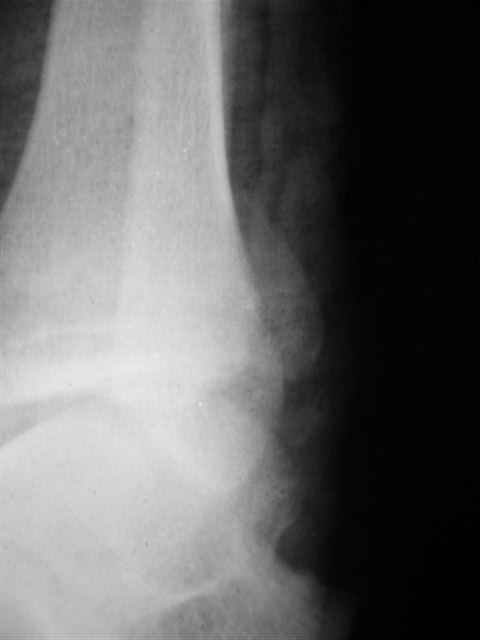

> интересуюсь тактикой лечения повреждений голеностопного сустава.

Ничего сверхъестественного, но если есть интерес, то в понедельник пересниму Рг-граммы и отправлю.

Я предупреждал, что ничего сверхъестественного. Каюсь, что одна из спиц прошла несколько дальше, чем нужно было, но главное - перелом стабилизирован и больной работает суставом в полном объёме, несмотря на представленную раннее травму коленного сустава.